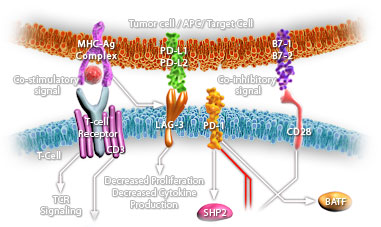

HSP90 is a highly conserved and essential stress protein that is expressed in all eukaryotic cells. Despite its label of being a heat-shock protein, HSP90 is one of the most highly expressed proteins in unstressed cells (1–2% of cytosolic protein). It carries out a number of housekeeping functions – including controlling the activity, turnover, and trafficking of a variety of proteins. Most of the HSP90-regulated proteins that have been discovered to date are involved in cell signaling. The number of proteins now know to interact with HSP90 is about 100. Target proteins include the kinases v-Src, Wee1, and c-Raf, transcriptional regulators such as p53 and steroid receptors, and the polymerases of the hepatitis B virus and telomerase. When bound to ATP, HSP90 interacts with co-chaperones Cdc37, p23, and an assortment of immunophilin-like proteins, forming a complex that stabilizes and protects target proteins from proteasomal degradation.

In most cases, HSP90-interacting proteins have been shown to co-precipitate with HSP90 when carrying out immunoadsorption studies, and to exist in cytosolic heterocomplexes with it. In a number of cases, variations in HSP90 expression or HSP90 mutation has been shown to degrade signaling function via the protein or to impair a specific function of the protein (such as steroid binding, kinase activity) in vivo. Ansamycin antibiotics, such as geldanamycin and radicicol, inhibit HSP90 function.